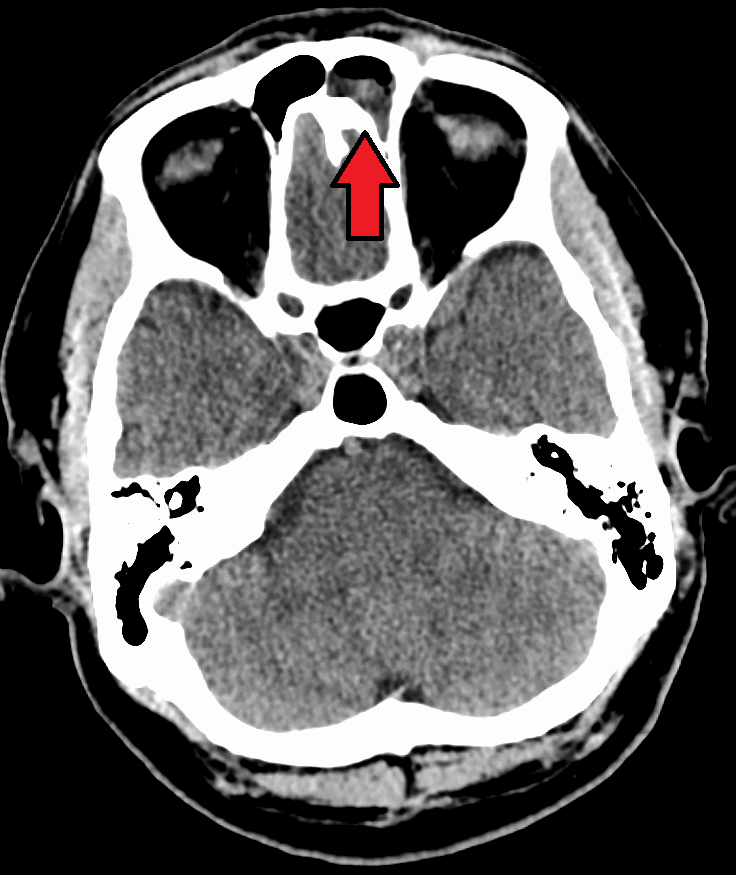

부비동염의 진단은 주로 콧물의 성상, 양, 그리고 호흡기 증상을 통해 이루어진다. 알레르기가 의심될 경우 알레르기 검사를 시행하며, 단층 촬영(CT)을 실시하기도 한다.[60] 의료 제공자는 관찰 대기를 통해 세균성 부비동염과 바이러스성 부비동염을 구별한다. 증상이 악화되지 않은 채 10일 미만 지속되면 바이러스성 감염으로 추정한다.[60] 반면, 증상이 10일 이상 지속되거나 그 사이에 악화되면 세균성 부비동염으로 간주한다.[63] 치아 통증과 구취 또한 세균성 질환을 시사하는 지표이다.[62]

합병증이 없다면 X-ray, CT, MRI와 같은 영상 촬영은 일반적으로 권장되지 않는다.[63] 부비동염으로 인한 통증은 상악 치아의 치수염(치통)으로 인한 통증과 혼동될 수 있으며, 그 반대의 경우도 마찬가지이다. 머리를 앞으로 숙일 때 통증이 심해지는 것은 부비동염을 치수염과 구별하는 특징적인 증상이다.

- X선 촬영, 컴퓨터 단층 촬영(CT)으로 부비동 내 고름 축적 여부를 확인한다.

만성 부비동염이 12주 이상 지속되면 CT 스캔을 받는 것이 좋다.[63] CT 스캔에서 급성 부비동 분비물은 10~25 하운스필드 단위(HU)의 방사선 밀도를 나타내지만, 만성 상태에서는 점성이 증가하여 방사선 밀도가 30~60 HU가 된다.[64]